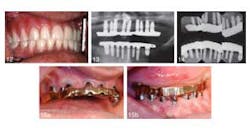

An article in the current issue of the Journal of Oral Implantology looks at long-term treatment for a patient with severe periodontal damage. The authors anticipate that the higher risk of implant failure in this patient will be offset by coating the implants with a rough, oxidized surface called TiUnite and by emphasizing the need for diligent oral hygiene. They also expect that by using overdenture prostheses instead of conventional removable dentures, they will improve stability and function — and thus patient satisfaction. Overall, increased use of implants has improved eating comfort and resulted in few complications after the surgery. However, pressure on implants is suspected to speed up loss of dense cortical bone in the jaw. Research has shown the TiUnite material stimulates bone growth, leading to faster fusion of implants and surrounding jawbone.RELATED | New material used in molar extraction sites optimizes bone regeneration and dental implant stability The current article is a case report on a 51-year-old patient who had been in a motorcycle accident and has a history of herpes, hepatitis, insulin-dependent diabetes, and persistent recurrent tooth decay. The patient’s remaining teeth (see photos below) were comprised of fractured crowns and older failing implants. The surgeons removed all of his teeth and old implants followed by the immediate insertions of new implants and stabilizing overdentures. Provisional implants were used for support during healing. Five months later, the interim provisional implants and prosthesis were removed and fabrication of a final restorative prosthesis was initiated.

RELATED | Atrophic patients have more options with new dental implant Despite the higher risk of implant failure due to his periodontal disease and diabetes, the patient’s implants have been in place for 12 years with no complications noted at routine checkups and cleanings. The patient has been instructed post surgery in proper use of floss threaders, deep-cleaning brushes, and an oral irrigator. His daily efforts to practice good oral hygiene improved his overall dental health. The patient was pleased with the results one week after the provisional implants were placed and was still happy with the surgery 12 years later. Little care and maintenance of the prostheses have been necessary.RELATED |Less invasive approach to dental implants allows heart patients to continue anticoagulation therapy The authors concluded that in this case the prostheses have been effective, predictable, and reliable. They contend that such positive results were only possible because the patient changed their at home oral care preventing plaque buildup and disease. Full text of the article “Twelve-year clinical and radiological results of a maxillary and mandible implant-retained bar overdentures carried out on oxidized (TiUnite) replace select implants: A clinical case,” Journal of Oral Implantology, Vol. 39, No. 6, 2013, is now available here. The Journal of Oral Implantology is the official publication of the American Academy of Implant Dentistry. For more information about the journal or society, please visit their website.